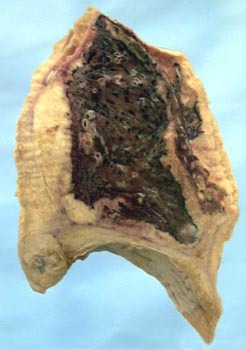

Below: mucous material, debris fills dilated airway